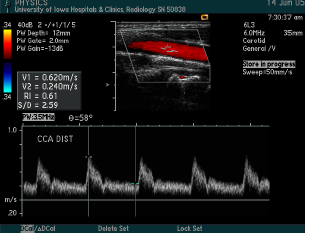

what measurements are taken?

what is calculated?

Common carotid artery

Internal carotid artery proximal

Internal carotid artery distal

External carotid artery

Vertebral

Subclavian

Peak systolic velocity, Peak end diastolic velocity

ICA/CCA ratio

what vessel is this waveform likely from?

CCA (below is distal CCA)